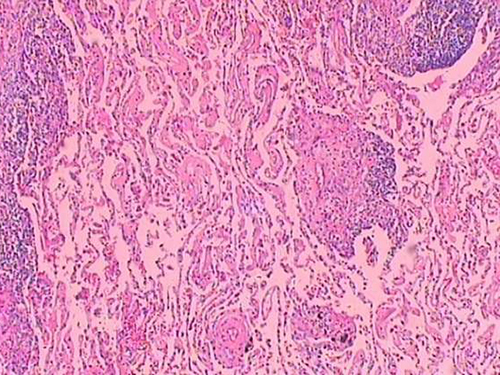

胸膜间皮瘤是一种起源于胸膜间皮或胸膜下结缔组织的肿瘤,近年来报告发患者数日趋增多。胸膜间皮瘤按其生长方式分为局限型和弥漫型。局限型胸膜间皮瘤多生在脏层胸膜,起病隐匿,早期多无症状,常在体检及X线检查时发现,因其多属良性,固手术切除效果良好,但也有潜在恶性或低度恶性,可恶变、复发和转移。弥漫型胸膜间皮瘤几乎均是恶性,长期接触石棉(包括开采、选矿和用石棉生产的产品)及吸烟,易诱发恶性胸膜间皮瘤,但此病发生与慢性脓胸或治疗气胸形成的胸膜瘢痕及与放射线接触也有密切关系。本病的男女之比为4:1,右胸腔比左胸腔常见。恶性弥漫型胸膜间皮瘤好发于壁层胸膜,无包膜,主要沿胸膜浸润扩张,使胸膜增厚,常累及脏层胸膜、心包、肺、对侧胸膜和胸壁、腹膜,局部侵犯和转移是多数患者的死亡原因。病理组织学分型以上皮型最多见(大于50%),肉瘤型最少(约占20%),其余为混合型。

3、胸膜活检

可直接窥见结节状态,并可直接钳取瘤组织,阳性率可达80%~90%。